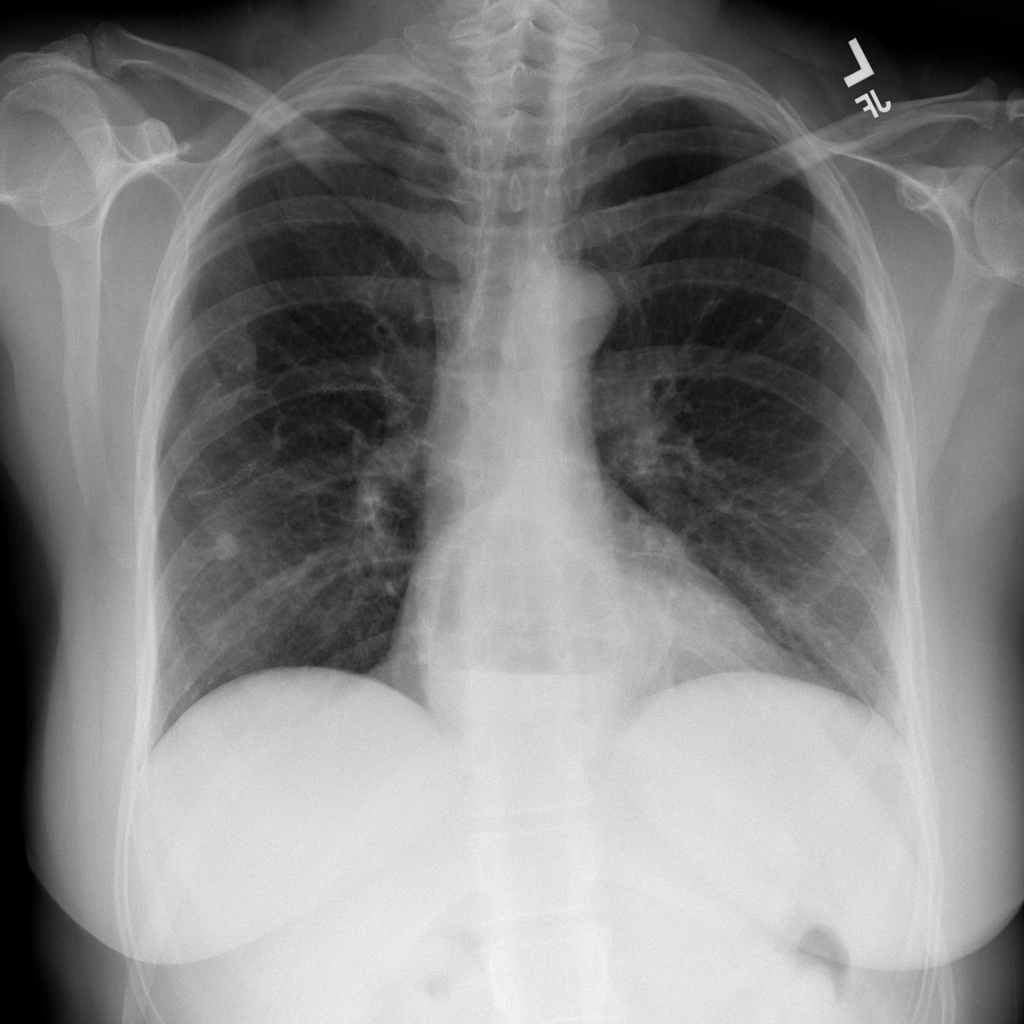

PAT-0ABD · IMG-000Hernia

PAT-0ABD · IMG-000

PA